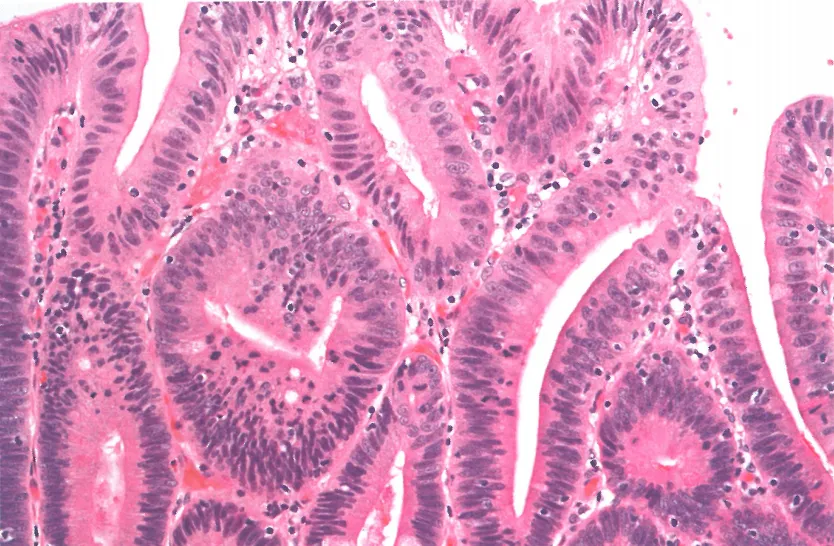

肠型低级别异型增生:可见肠型分化的高柱状细胞,细胞核呈细长形态且基本位于细胞中央

胃型低级别异型增生:小凹分化的高柱状细胞;细长细胞核位于基底

胃型异型增生